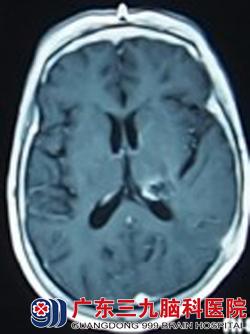

66岁的王女士因反复头晕1个月,在当地检查怀疑为脑肿瘤,为求进一步治疗而来到广东三九脑科医院。入院结合头部检查考虑为左侧基底节丘脑肿瘤(考虑为淋巴瘤可能性大),完善相关检查后在全麻下行左侧基底节、丘脑肿瘤穿刺活检术,术中冰冻病理考虑恶性肿瘤,淋巴瘤可能性大。术后王女士呈嗜睡状态,精神较差、烦躁,考虑为肿瘤进展快速所致,在与家属充分沟通告知病情后,果断为其行抢救性放疗以改善症状,避免病情恶化。放疗2次后王女士精神状态好转,烦躁情况较前改善。抢救性放疗3天后病理回报为弥漫大B细胞淋巴瘤,诊断明确,治疗予同步放化疗,随后行全脑放疗、适形放疗。治疗完毕后王女士各项生命体征平稳,神志清楚,无其他不适症状。治疗后一个月回院复查见其康复良好。

放疗前 放疗后1个月复查肿瘤消失